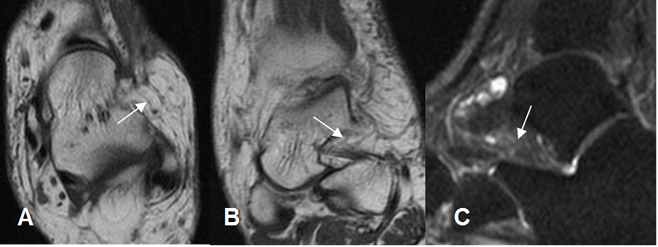

Fig 107. Seno del tarso normal.

A: RM axial y B: RM coronal en T1 y C: RM Sagital en STIR. Espacio del seno ocupado por tejido graso. (Flechas).